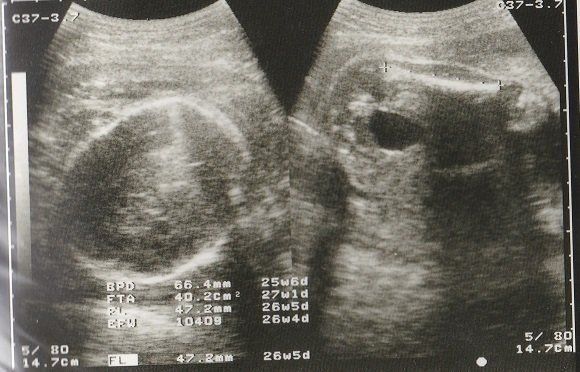

ちゃじゅびさんの妊娠26週目のエコー写真 男の子であることが判明

左側のエコー画像に、男の子のシンボルが写っています。人によっては、生まれるまで男の子か女の子か告げて欲しくないという方もいらっしゃるようですが、私の場合、お医者さんに何も聞かれずに「男の子ですね」と言われました。

左側は頭の画像。赤ちゃんの頭もだいぶ大きくなりました。